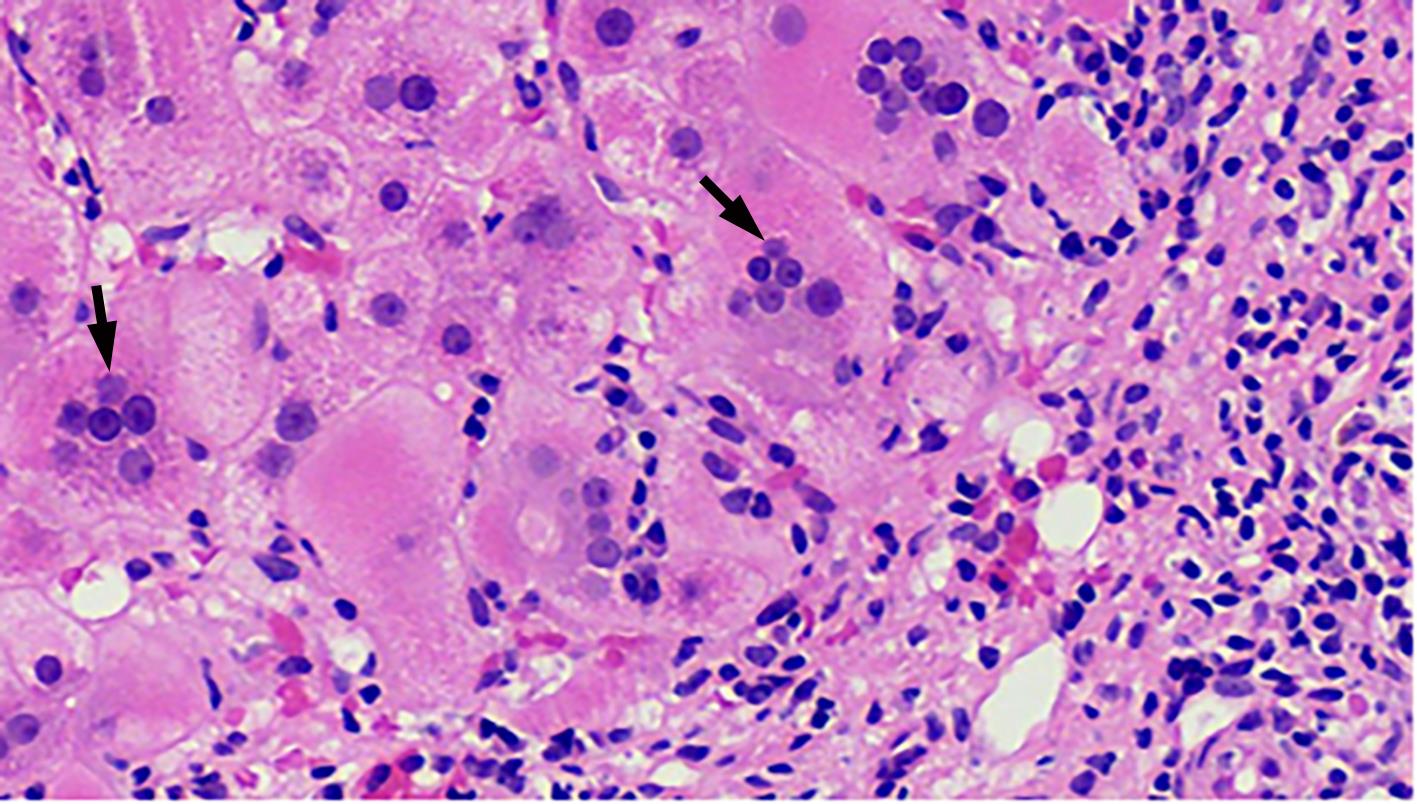

自身免疫性肝炎(AIH)是免疫介导的肝实质炎症性疾病,以高丙种球蛋白血症、自身抗体阳性和典型的肝组织学异常为特征。然而,AIH临床表现多样,缺乏特异性的血清学标志物,因此AIH的诊断困难,具有挑战性。虽然汇管区淋巴浆细胞浸润、界面性肝炎、淋巴细胞穿入现象和肝细胞玫瑰花结为AIH典型的组织学特征,但在AIH中尚可观察到其他的一些形态学改变,包括小叶中心性坏死、Kupffer细胞内透明小球等。所以没有一个单一的组织学特征可直接诊断AIH,需结合临床和实验室检查,并排除其他原因引起的肝脏疾病,方可做出正确的诊断。本文总结了AIH的组织学特征、不同的病理组织学谱、常见的临床问题、主要的鉴别诊断和最新进展。

Abstract:Autoimmune hepatitis (AIH) is an immune-mediated inflammatory disease of the liver parenchyma, which is characterized by hypergammaglobulinemia, the presence of autoantibodies, and typical abnormalities in liver histology; however, the diverse clinical manifestations of AIH and the lack of specific serological markers have brought difficulties and challenges in the diagnosis of AIH. Although portal lymphoplasmacytic infiltration, interface hepatitis, lymphocyte emperipolesis, and hepatocyte rosettes are the typical histological features of AIH, many other histological features can also be observed in AIH, including centrilobular necrosis and Kupffer cell hyaline globules. Therefore, no single histological feature can be used for the diagnosis of AIH, and a confirmed diagnosis should be made with reference to clinical and laboratory examinations, with the exclusion of liver diseases due to other causes. This article summarizes the histological features of AIH, different histopathological spectrum, common clinical issues, differential diagnosis, and recent advances.